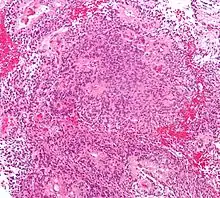

| Micrograph of an ependymoma. H&E stain. | |

Ependymomas are composed of cells with regular, round to oval nuclei. There is a variably dense fibrillary background. Tumor cells may form gland-like round or elongated structures that resemble the embryologic ependymal canal, with long, delicate processes extending into the lumen; more frequently present are perivascular pseudorosettes in which tumor cells are arranged around vessels with an intervening zone consisting of thin ependymal processes directed toward the wall of the vessel.[4]

It has been suggested that ependymomas are derived from radial glia, despite their name suggesting an ependymal origin.[5]